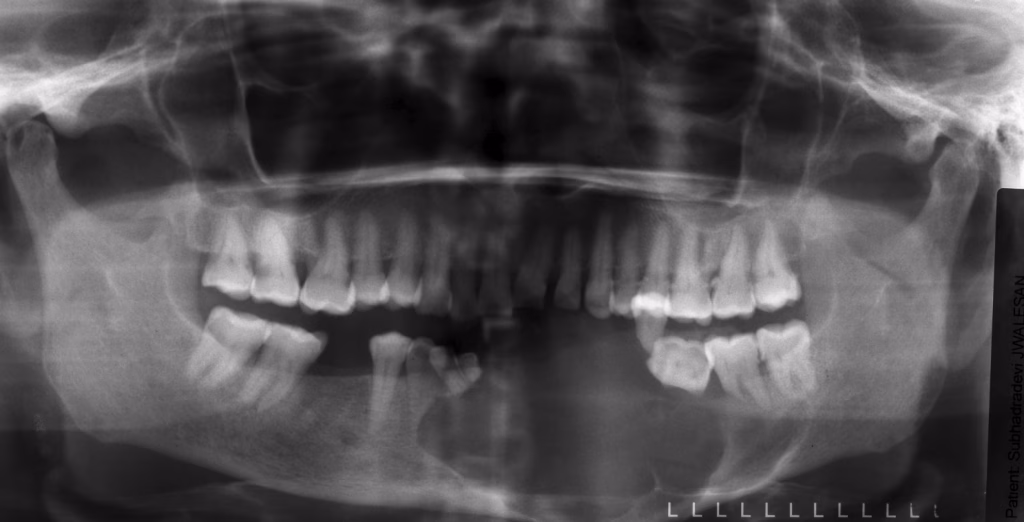

While the word “tumor” can sound frightening, benign odontogenic tumors are slow-growing, treatable, and rarely life-threatening. Dentists usually find them early during routine X-rays.

- A finding on an X-ray with no symptoms at all

- A cyst-like area on X-rays

- Looks like a simple cyst on X-ray

- Shows small “white spots” inside the lesion on X-rays

- Looks like a simple cyst on X-rays

- Looks like tiny miniature teeth on the X-ray

- Appears as a solid, mixed-up mass of tooth material

A “honeycomb” or “tennis racket” pattern on X-ray.

- A round, well-defined area on X-ray

- A bright, round mass fused to the tooth root on X-ray

- Shows a well-defined border with mixed radiolucent/radiopaque areas